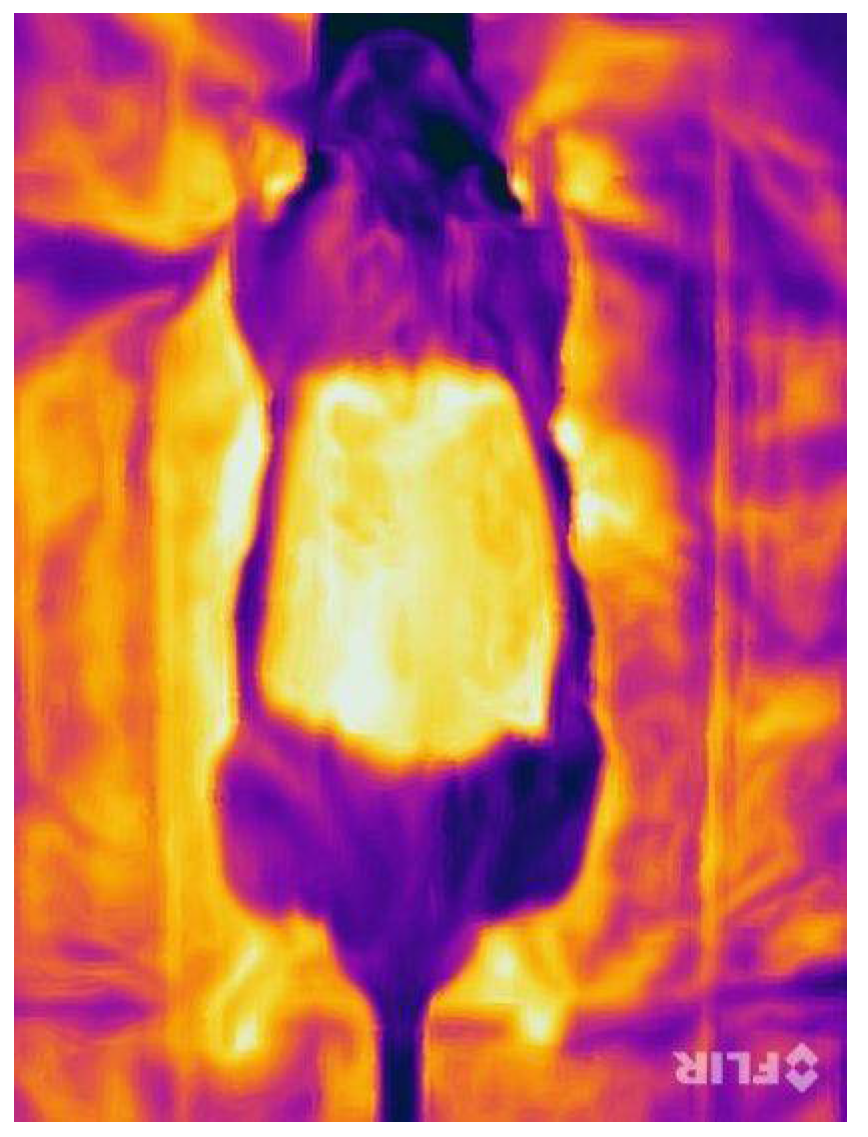

3.5. Near-Infrared Reflectance-Based Imaging and Infrared Thermography